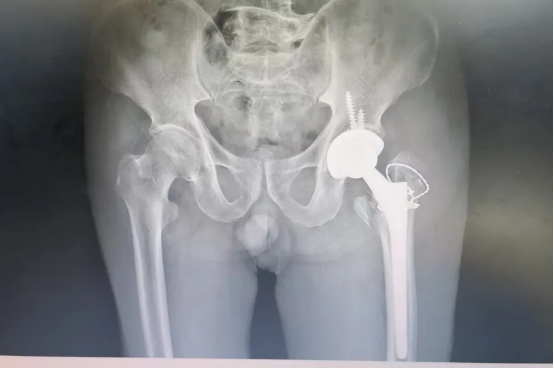

术后摄片